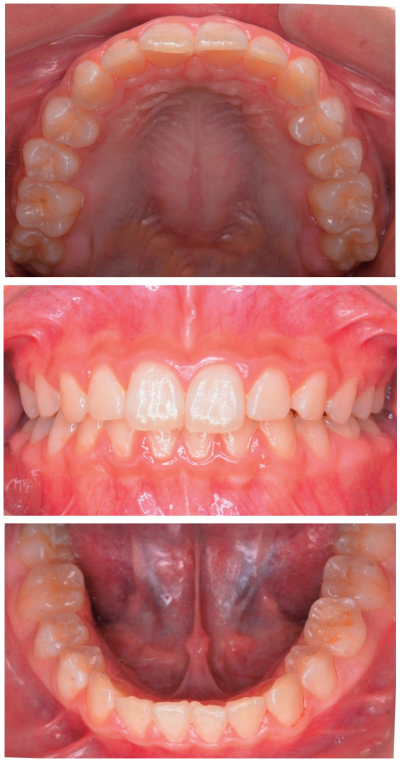

14歳の男子。下顎左側第二乳臼歯が交換しないため精査を希望して来院した。3年前から気付いていたがそのままにしていたという。初診時の口腔内写真、エックス線写真及び歯科用コーンビームCTを別に示す。